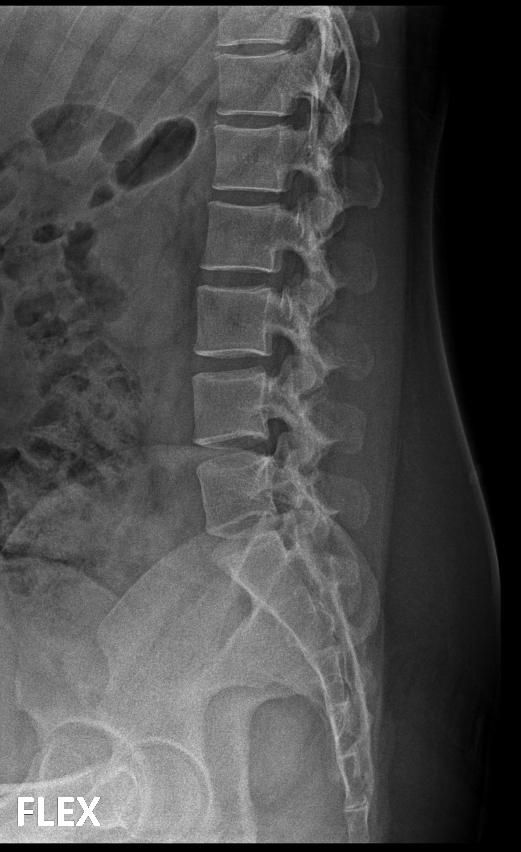

척추분리증인가요??(엑스레이 있어요)

한 병원에서는 척추분리증이라고 하고 한 병원에서는 척추분리증이 아니라고 해서요. 혹시 아래 사진에서 척추분리증 소견이 보이는 사진이 있나요??

여기까지가 a병원에서 찍은 사진이고 아래가 b병원에서 찍은 사진이에요!

A병원 세번째 사진의 아래 부위에 척추분리증이 있는게 맞습니다.

B병원 사진에서는 비교적 흐리게 보이지만 잘 보면 B병원 엑스레이에서도 같은 부위에 분리증을 확인할 수 있습니다.

두 사진을 비교해서 보았을 때 큰 문제가 있어 보이지는 않으며 엑스레이상 척추분리증 진단이 어렵거나 애매한 경우에는 추가적인 검사 MRI를 통해 진단을 받아보시는 것도 방법이라고 생각합니다.

제가볼때 엑스레이상에 분리증은 보이지않지만 각도에따라 그리고 기계에따라서 달라질수있으니 정확하게 하고싶다면 MRI검사를 추천합니다 감사합니다~

두가지 사진을 비교해보았을 때, 크게 특징적인 것이 관찰되지는 않습니다. 척추분리증을 진단하는 것은 임상증상과 영상검사를 통한 구조적 이상을 확인하는데요, 정확한 검진을 위해서는 ct나 mri같은 검사를 고려하시거나, 척추질환을 전문적으로 진단하는 병원급 의료기관에 방문해보시는 것도 고려해보시면 좋겠습니다.